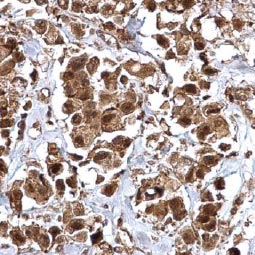

Cancer Stem Cell Markers |